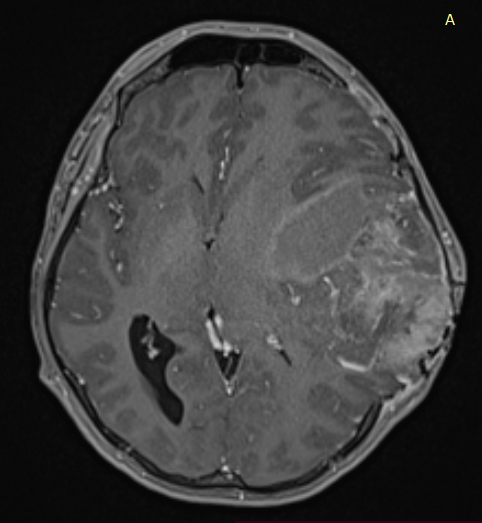

Temporal ependymomas are exceedingly rare intracranial neoplasms originating from ependymal cells within the temporal lobe. The rare nature of these tumours makes diagnosis and treatment extremely difficult in the field of neuro-oncology. These tumours frequently encounter misdiagnosis as meningiomas or other extra-axial lesions due to their atypical location and the absence of distinctive features. Consequently, histopathological examination becomes essential for accurate evaluation and a precise diagnosis. This article presented a unique case of a 25-year-old male patient’s supratentorial ependymoma at the temporal region. The report described the patient’s clinical presentation, including progressive headaches, abnormal behaviour and vomiting, leading to timely diagnostic investigations. After a surgical resection, the diagnosis of ependymoma was confirmed by histopathological analysis. Following surgery, the patient defaulted follow-up and presented six months later with worsening symptoms. Radiological imaging proved the tumour’s significant growth. The second resection worsened his neurological deficits. Unfortunately, adjuvant radiotherapy would not be beneficial to him at this point. He received palliative care. The case study emphasises the difficulty in diagnosing and treating temporal ependymomas, underscoring the importance of multidisciplinary collaboration and evidence-based approaches for optimal patient outcomes.